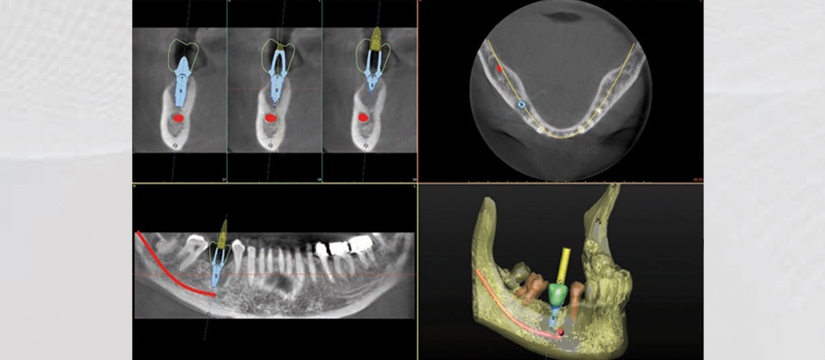

- Panoramic View

- 3D Detntition Positioning